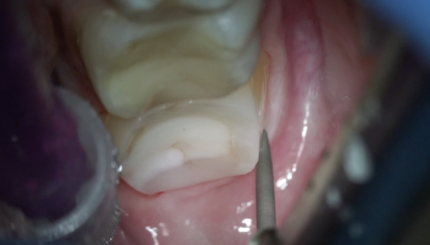

34,35,36,37КЕРАМИЧЕСКИЕ НАКЛАДКИ,ПРЕПАРИРОВАНИЕ,РЕТРАКЦИ,ОТТИСК

26 сентября 2024